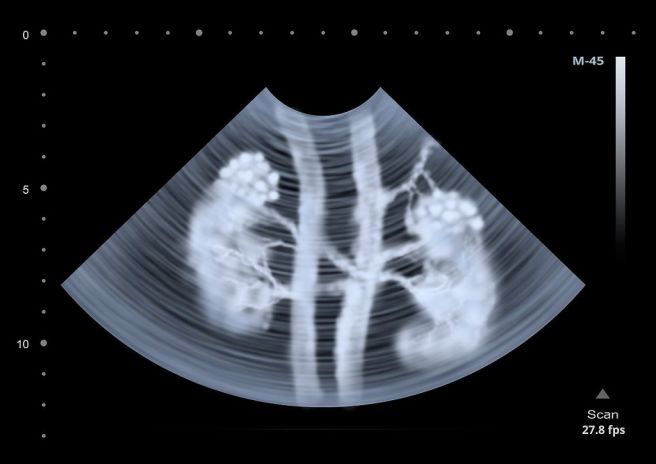

일부 콩팥 물혹은 유전적 소인과 관련이 있습니다. 특히 다발성 낭종 신질환은 유전자 돌연변이로 인해 발생하는 대표적인 질환입니다.

양쪽 신장에 다수의 물혹이 발생하며, 시간이 지남에 따라 크기와 수가 증가할 수 있습니다. 가족력이 있는 경우 콩팥 물혹 발생 위험이 높아질 수 있으므로 주의가 필요합니다.